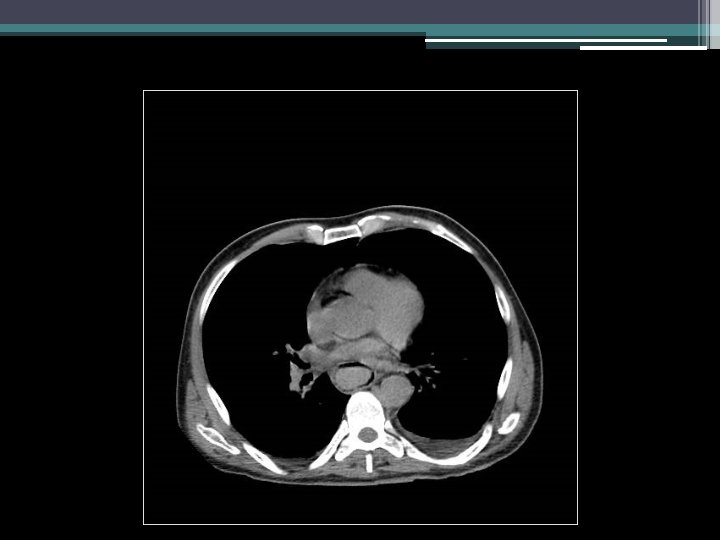

Gastric emphysema • Diagnosis: gastric emphysema due to gastric outlet obstruction • Pneumatosis intestinalis ▫ Gastric pneumatosis Gastric emphysema Emphysematous gastritis ▫ Pneumatosis coli

What is pneumatosis intestinalis? • First described in 1754 by Du Vernoy • Presence of extraluminal bowel gas within bowel wall • Breakdown of mucosal and immunological barrier of intestine, especially in the setting of increased intraluminal pressure Galundiuk S et al. DCR. 1986; (29)5: 358 -363. Heng Y et al. Am J of Gastroenterol. 1995; (90)10: 1747 -1758. Koss LG. Arch Pathol. 1952; (53): 523 -549.

What is pneumatosis intestinalis? • • 0. 03% in general population (autopsy series) Incidence rising with increasing CT use Most asymptomatic, incidentally detected Complications occur in up to 3% of patients ▫ Pneumoperitoneum, bowel obstruction, volvulus, intussusceptions, hemorrhage Galundiuk S et al. DCR. 1986; (29)5: 358 -363. Heng Y et al. Am J of Gastroenterol. 1995; (90)10: 1747 -1758.